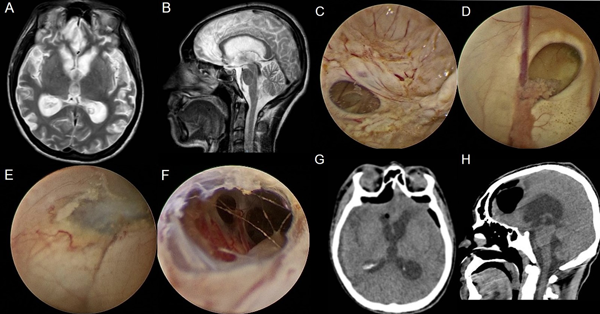

Se presentan en figuras 8 a 12 los casos ilustrativos más representativos de nuestra serie.

Figura 12: Hidrocefalia en contexto de malformación de vena de Galeno. Paciente con válvula previa, se ingresa por izquierda: A-B) RM preoperatoria. C-F) Hallazgos intra-operatorios. G-H) RM postoperatoria.